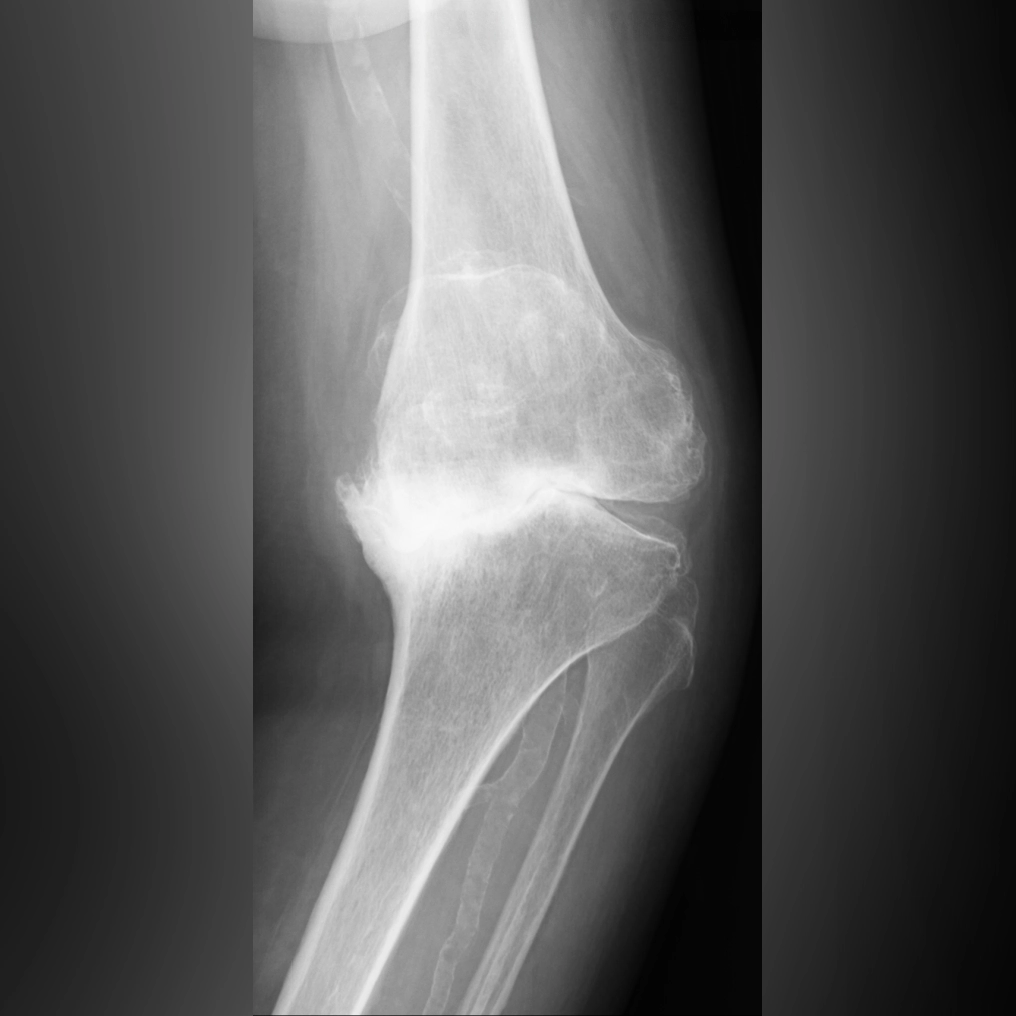

末期では、脛骨がすり減り、大腿骨がめり込んだ状態になります。ここまで変形が進むと、ひざの中にある4つの靱帯のバランスも悪くなり、歩行が不安定になってしまいます。